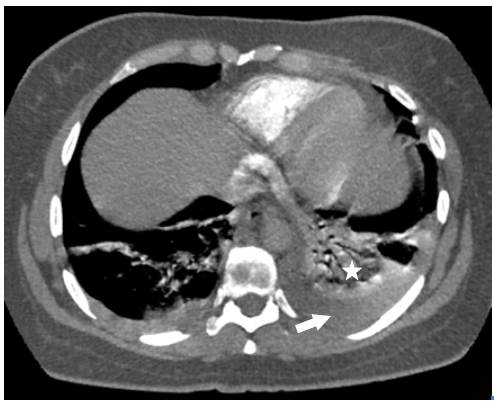

The following tests were performed: blood count, electrolytes, blood urea nitrogen (BUN) and creatinine, which were within normal limits. On the other hand, the electrocardiogram showed sinus tachycardia, while the echo-cardiogram had a structural and functionally normal heart. Finally, the chest X-ray revealed left basal lamellar atelectasis and right atrium growth (Figure 1).

Posteroanterior chest X-ray. Image in left basal band corresponding to atelectasis (arrow).

Fig 1: Posteroanterior chest X-ray. Image in left basal band corresponding to atelectasis (arrow).